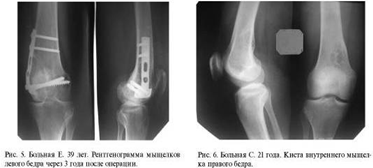

Пациент Б., 28 лет. Послеоперационный

остеомиелит правой большеберцовой кости, формирующийся ложный сустав. В область

ложного сустава сделана инъекция «ЛитАр». Через 4 месяца произошла надежная

консолидация костных отломков (рис. 4 а, б).